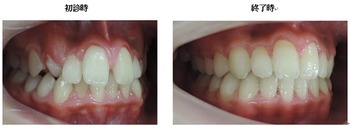

よく診る、難しい症例(奥歯の隙間)

今回の症例は、悪い歯並びの代表例である八重歯です。

歯並びが悪いだけでなく、困ったことに犬歯から奥歯にかけて歯が嚙み合っていない開咬の状態です。

一般的な矯正の治療法では中心から4番目の歯を抜いて隙間をつくり、飛び出した犬歯を並べて治療します。

しかし、この矯正方法は歯を横に動かす治療法なので、噛んだときにできる奥歯の上下の隙間を治すのが苦手です。

当院ではマルチループ(MEAW法)という上の写真で装着しているようなクネクネ曲がったワイヤーを使用して、上下の隙間を埋めていくことで歯並びを整えます。